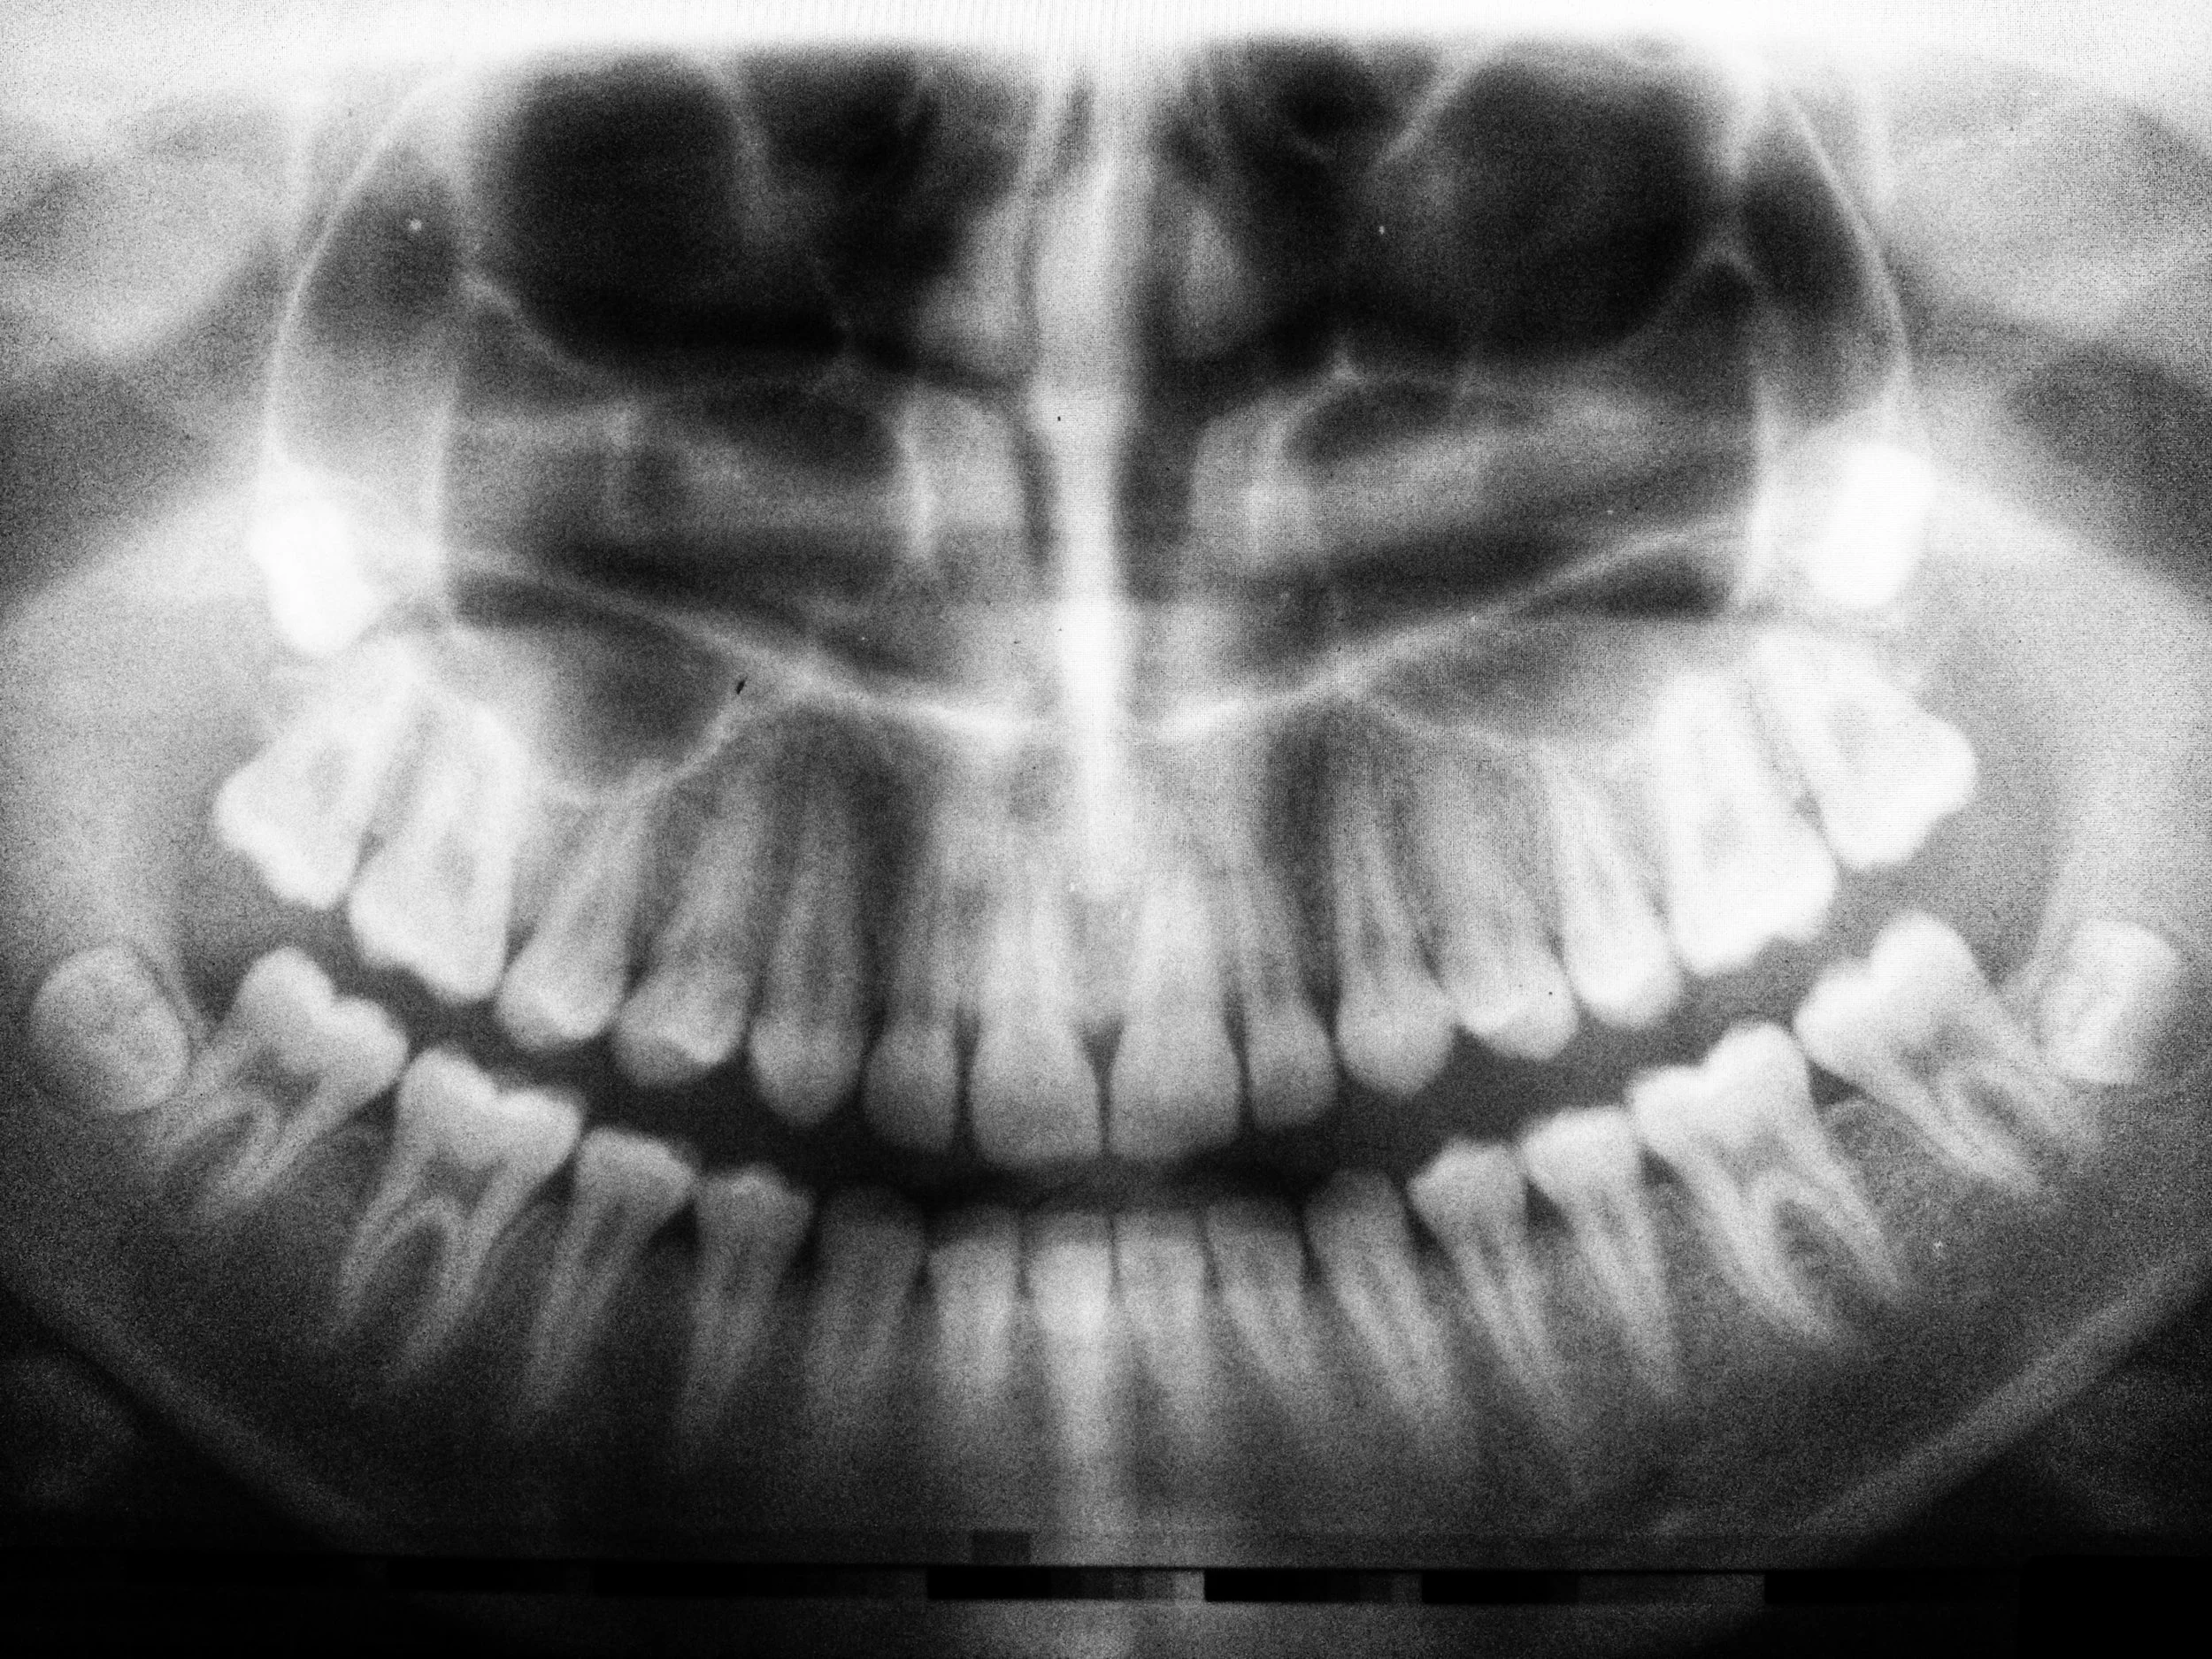

A root canal treatment is a straightforward and tooth-saving procedure that addresses infection within your tooth's pulp, the soft tissue inside.

We carefully remove the damaged nerve, clean the inner canal(s), and seal it with a biocompatible material to prevent further issues. We often place a protective crown or onlay afterwards which helps to strengthen the tooth.